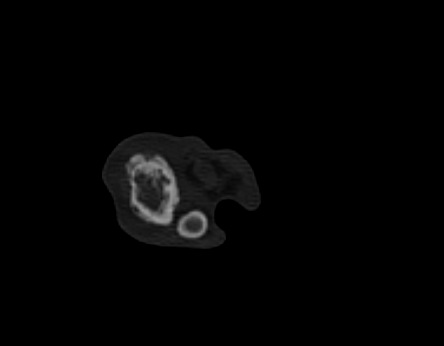

Strahlentherapie bei Bruno

Glück im Unglück: Brunos Besitzer:innen haben die Probleme sehr früh erkannt und die Diagnostik wurde sehr zügig durchgeführt. So zeigte sich der Knochen ausreichend stabil für eine stereotaktische Strahlentherapie, eine Amputation lehnten die Besitzer nach ausführlicher Aufklärung ab. Der erste Termin dient hier neben der Vorbesprechung und Aufklärung vor allem der Anfertigung einer Computertomographie zur Bestrahlungsplanung. Da bislang keine CT vorlag wurde auch ein Thorax-CT zur Metastasensuche angefertigt, welche glücklicherweise negativ war. Bruno wurde in drei Fraktionen bestrahlt und auch er hat die Narkosen erwartungsgemäß gut vertragen. Innerhalb der ersten drei wöchentlichen Follow-Ups berichteten die Besitzer bereits von einer moderaten Schmerzreduktion. In Summe muss man diese natürlich als Kombination aus Strahlentherapie und medikamentöser Therapie sehen; Bruno erhielt ein Amantadin-Derivat, Gabapentin und ein NSAID als Kombinationstherapie. Eine Chemotherapie wurde seitens der Radioonkologie angeraten, zur entsprechenden Beratung erfolgte eine Rücküberweisung an die erstbehandelnde Tierklinik. Nach umfassender Aufklärung entschieden sich die Besitzer:innen ganz bewusst gegen eine Chemotherapie. Die Problematik der kontaminierten Ausscheidungen hätte umfassende Einschränkungen in Brunos Alltag als Hofhund bedeutet. Viele Freiheiten und seine umfassende Selbstständigkeit wären nicht mehr möglich gewesen, was für die Halter:innen keine Option war. Acht Monate nach Ende der Strahlentherapie ist Bruno mit Begeisterung in den Weinbergen unterwegs und kümmert sich weiter pflichtbewusst um den Hof.